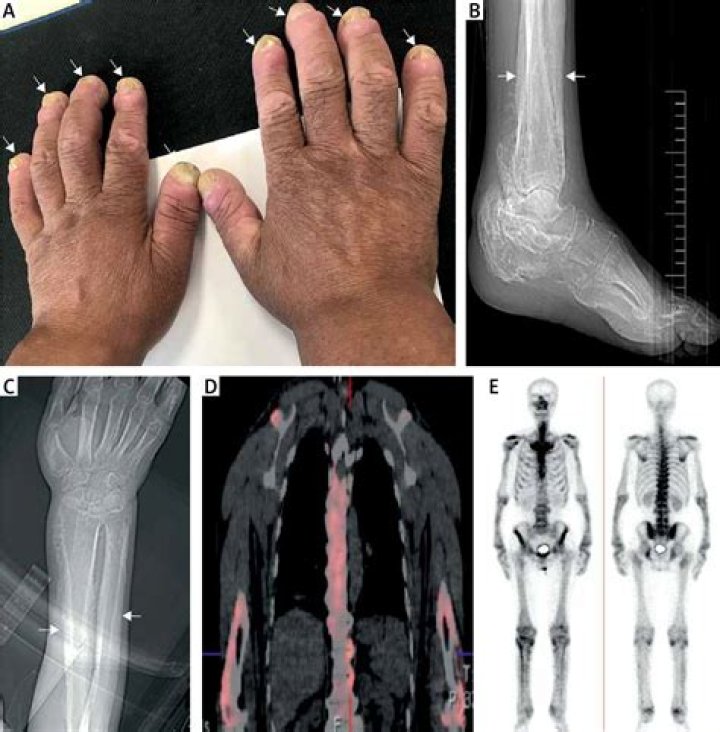

Hypertrophic osteoarthropathy (HOA) is mainly caused by mainly fibrovascular proliferation. It is characterized by a combination of clinical findings, including severe disabling arthralgia and arthritis, digital clubbing, and periostosis of tubular bones with or without synovial effusion.

Hypertrophic osteoarthropathy (HOA) is a syndrome characterized by clubbing of the digits, periostitis of the long (tubular) bones, and arthritis. It is also known as pachydermoperiostosis (PDP). HOA can be primary (hereditary or idiopathic) or secondary.

Definition. Clubbing is a physical sign characterized by bulbous enlargement of the ends of one or more fingers or toes (Figure 44.1). Proliferation and edema of connective tissue result in loss of the normal angle between the skin and nail plate and excessive sponginess of the nail base.

It can be graded into 5 stages i.e. Grade 1: fluctuation and softening of the nail bed, Grade 2: increase of the hyponychial angle, Grade 3: accentuated convexity of the nail, Grade 4: clubbed appearance of the fingertip, and Grade 5: development of a shiny or glossy change in nail and adjacent skin1.